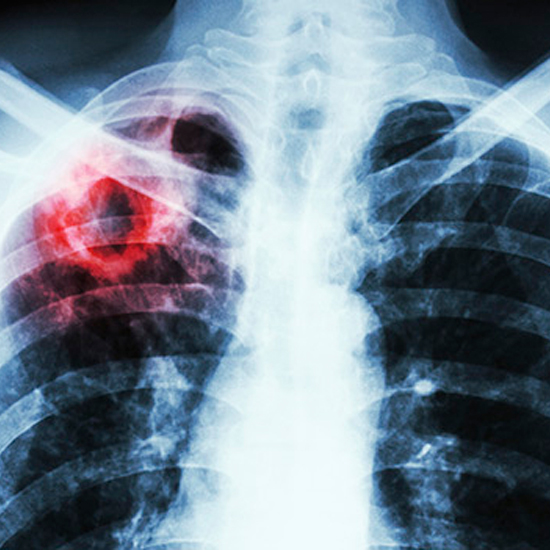

Як ми вже повідомляли, Міністерство охорони здоров’я України оприлюднило наказ від 6.10.2021 р. № 2161 «Про внесення змін до стандартів охорони здоров’я при туберкульозі». У МОЗ України зазначають, що головна мета документа — застосування кращих міжнародних підходів у сфері надання медичної допомоги хворим на туберкульоз.

Іншими словами, Україна продовжує впроваджувати доказові методики лікування відповідно до європейських стандартів Всесвітньої організації охорони здоров’я. Українського пацієнта лікуватимуть так, як його лікували б у будь-якій іншій країні Європи.

Втілення положень наказу дозволить підвищити показник ефективності та якості лікування туберкульозу, в тому числі лікарськостійкого та забезпечить зниження показника захворюваності, смертності та поширеності, а також сприятиме зменшенню невиправданих витрат та ризиків для пацієнтів.